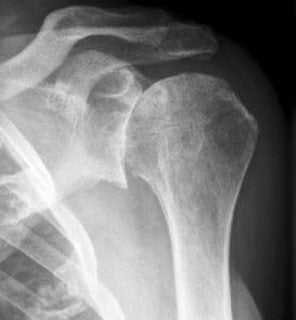

МРТ плечевого сустава в косой продольной проекции в норме

Первая из 24 последовательных Т1-взвешенных МР-томограмм правого плечевого сустава в косой продольной проекции с направлением срезов от медиальной стороны к латеральной. Томограммы получены с использованием плечевой катушки на 3Т МР-томографе. В наиболее медиальный срез попадает латеральный отдел легкого и грудная стенка. Широчайшая мышца спины покрывает нижнюю поверхность большой круглой мышцы. Эти мышцы сложно различить как отдельные структуры. Обе мышцы проходят в верхнелатеральном направлении и прикрепляются к гребню малого бугорка. К мышцам вращательной манжеты плеча относятся надостная, подостная, малая круглая и подлопаточная. Все мышцы вращательной манжеты начинаются от лопатки. Лопаточно-подъязычная мышца начинается от верхнего края лопатки. Она состоит из верхнего и нижнего брюшек. Верхнее брюшко прикрепляется к нижнему краю подъязычной кости. Лопатка имеет Y-образную форму вследствие наличия направленной кзади ости лопатки. В норме надостная мышца полностью находится внутри «Y» и заполняет весь ее объем, если не развивается атрофия мышцы. У верхней поверхности плечевого сустава можно увидеть часть трапециевидной мышцы. Трапециевидная мышца прикрепляется к верхнему краю латерального отдела ключицы, медиальному краю акромиона и верхнему краю ости лопатки. Дельтовидная мышца прикрепляется к тем же костным структурам рядом с трапециевидной мышцей, только к противоположной стороне каждой из костей (нижнему краю латерального отдела ключицы, латеральному краю акромиона и нижнему краю ости лопатки). Подлопаточная мышца заполняет подлопаточную ямку лопатки. Подостная и малая круглая мышцы расположены ниже ости лопатки. Подостная мышца крупнее и лежит выше малой круглой мышцы. Надостная, подлопаточная, малая круглая и подостная мышцы (по часовой стрелке) продолжаются в латеральном направлении. Сухожилия подостной и надостной мышц соединяются у латеральной поверхности головки плечевой кости. Ость лопатки заканчивается у акромиального отростка. Начинает визуализироваться акромиально-ключичный сустав. Сосудисто-нервный пучок проходит вдоль передней поверхности подлопаточной мышцы. Срез на уровне суставной впадины лопатки. Виден темный край проходящей по окружности суставной губы. От клювовидного отростка начинаются клювовидно-плечевая мышца и сухожилие короткой головки двуглавой мышцы. Суставно-плечевые связки визуализируются в виде пучков ткани с низкой интенсивностью сигнала, окружающих переднюю, нижнюю и задненижнюю поверхности плечевого сустава. Суставно-плечевые связки укрепляют капсулу сустава. Срез на уровне медиального края головки плечевой кости. Задняя артерия, огибающая плечевую кость, огибает шейку плечевой кости и анастомозирует с передней одноименной артерией. Вращательный интервал представляет собой треугольное пространство, ограниченное сверху передним краем сухожилия надостной мышцы, снизу—верхней поверхностью сухожилия подлопаточной мышцы, с медиальной стороны—основанием клювовидного отростка, а с латеральной стороны—сухожилием длинной головки двуглавой мышцы в межбугорковой борозде. Сухожилие длинной головки двуглавой мышцы начинается от над-суставного бугорка у верхнего края суставной впадины. На этом изображении оно проходит в дистальном направлении над головкой плечевой кости, окруженное синовиальной оболочкой. Сухожилие прободает капсулу сустава через отверстие, расположенное около межбугорковой борозды. На уровне середины головки плечевой кости дельтовидная мышца покрывает наружную поверхность плечевого сустава. Оценивать морфологический тип акромиального отростка лучше всего на первом срезе латеральнее акромиально-ключичного сустава. Вращательная манжета на уровне латеральной поверхности головки плечевой кости состоит преимущественно из сухожилий. Сухожилия начинают срастаться друг с другом и суставной капсулой. Уровень срезов приближается к латеральной поверхности головки плечевой кости. Сухожилия вращательной манжеты образуют непрерывный ободок тканей над головкой плечевой кости, а затем продолжаются в латеральном направлении. На этой Т1-взвешенной томограмме сигнал от сухожилий вращательной манжеты имеет более высокую интенсивность вследствие развития феномена «магического угла», в отличие от низкой интенсивности сигнала от сухожилий в норме. Нормальный сигнал от сухожилий можно увидеть при получении томограмм в режимах с большим эхо-временем. Сухожилия вращательной манжеты приближаются к месту прикрепления в области большого и малого бугорков. Сухожилие подлопаточной мышцы прикрепляется к малому бугорку и образует крышу межбугорковой борозды. Сухожилия надостной, подостной и малой круглой мышц прикрепляются к большому бугорку — к верхней, средней, и нижней поверхностям соответственно. Все еще видно прикрепление небольшой части пучков надостной и подостной мышц к большому бугорку. Наиболее латеральная поверхность плечевого сустава полностью покрыта средними пучками дельтовидной мышцы.